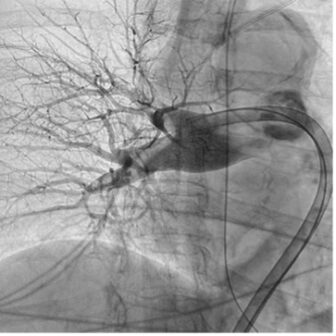

Bilateral common femoral vein access was obtained. The right-sided access was primarily used to facilitate thrombectomy, and the left-sided access was obtained to provide a rail for up-and-over sheath and catheter advancement in anticipation of potential lower extremity thrombectomy. A 17-F, 65-cm Element™ sheath was advanced into the right PA, and a right-sided thrombus affecting multiple segmental branches was identified. The 16-F Lightning Flash 3.0 catheter was advanced over a Rosen wire into the right PA, and aspiration was turned on; near-immediate evacuation of the target thrombus was achieved and confirmed by follow-up angiography. Following successful pulmonary thrombectomy, a decrease in PA pressure was noted.

Angiogram of pulmonary thrombus Angiogram of pulmonary thrombus

Pre—Angiogram showing right-sided pulmonary thrombus.